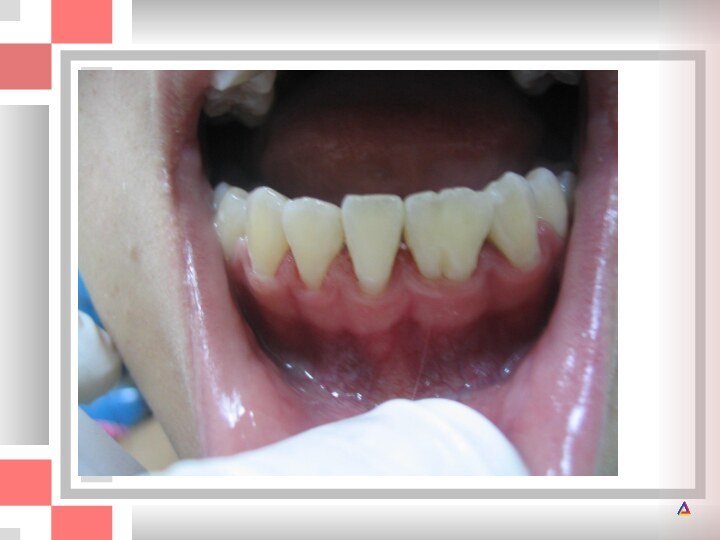

А - перелом коронки верхнего левого центрального резца по II классу;

по II классу; Б - через 7,5 лет после реставрации.

Приемлемый функциональный и эстетический результат, хотя при внимательном осмотре можно обнаружить стирание режущего края пломбы.